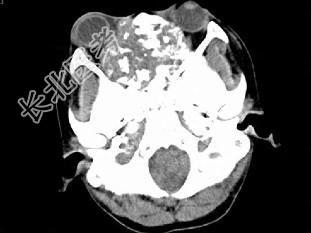

- 单项选择题男,26岁, 进行性鼻腔阻塞、流涕来院就诊,近两年持续性头痛、头晕.如图所示筛窦区占位灶应诊断为 ( )

A、脊索瘤伴左上颌窦炎

B、软骨瘤伴左上颌窦炎

C、骨化性纤维瘤伴左上颌窦炎

D、骨结核伴左上颌窦炎

E、骨纤维异常增殖症伴左上颌窦炎